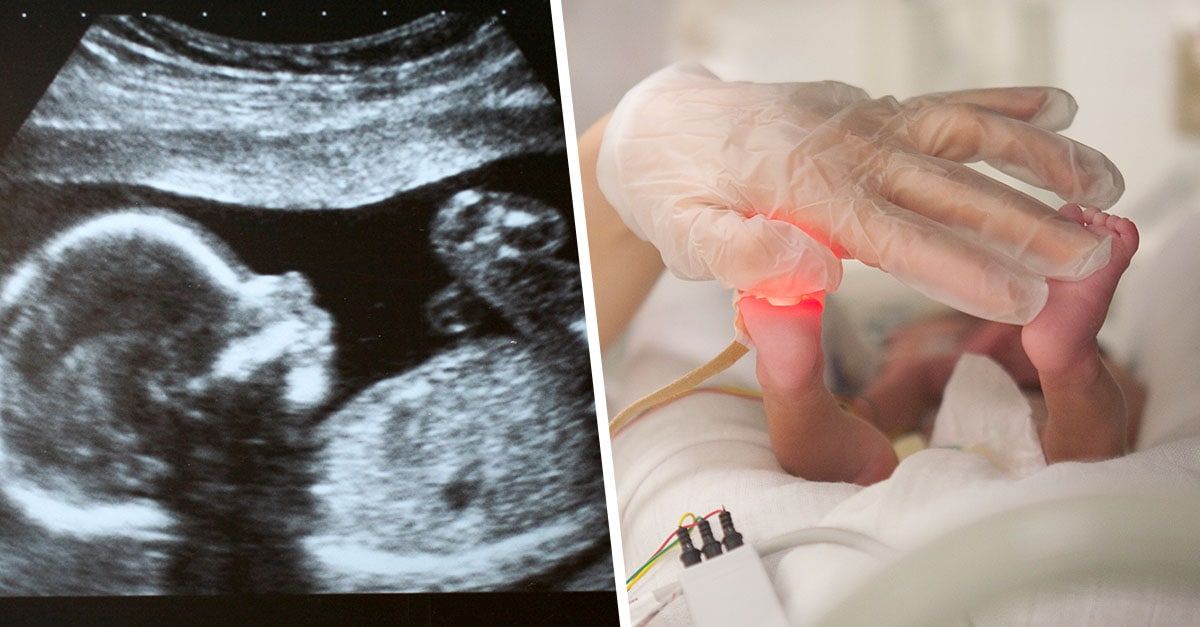

A baby boy that was born seventeen weeks early has survived after his parents refused to turn off his life support.

Back in June 2021, Chay Jefferys was born seventeen weeks early at just at twenty-three weeks where he weighed just 1lb.

According to the Metro, when Chay was born he was inside of his amniotic sack and had to be resuscitated by medics before being rushed to intensive care.

“It was so scary, Chay was so tiny, he fit in the palm of my hand,” McGee said. “I just thank my lucky stars he wasn’t born just a few days earlier as he wouldn’t have made the cut off point as babies born at 23 weeks are usually deemed too premature for doctors to treat.”